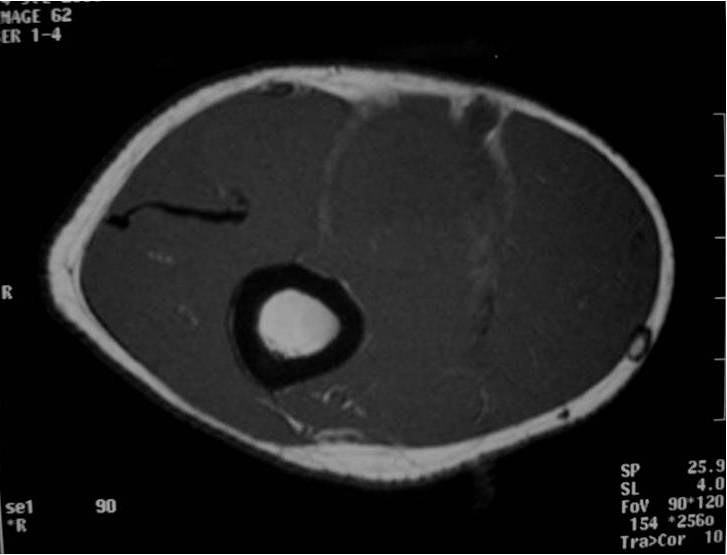

MRI appearance (Fig. 1 – 4)

• Intermuscular mass closely related to a neurovascular bundle with a distinct margin surrounded by rim of fat (split fat sign)

• Fusiform, elongated cigar shaped mass

• Nerve: Tubular structure visualized entering and exiting the mass (may be difficult to see with small lesions or lesions of the trunk or retroperitoneum) (Fig. 2 & 4)

• Spinal lesions: usually dumbell shaped exiting from and enlarged neural foramina

• T1: Isointense to muscle; Variable enhancement with gado

• T2: High signal (myxoid areas) with some heterogeneity (Fig. 3)

o Target Sign: Low signal central area (cellular/collagenous area; Antoni A) and high signal peripheral area (myxoid area; Antoni B)

Fig. 1-4 MR image demonstrates a 5 cm intermuscular mass in the anterior compartment of the arm arising along the course of the neurovascular structures. Isointense to muscle on T1W image and heterogeneous high signal on T2W with low signal in the central area (Antoni A) and peripheral high signal (Antoni B), known as “Target Sign”. Coronal image shows a structure entering and exiting the mass (median nerve).